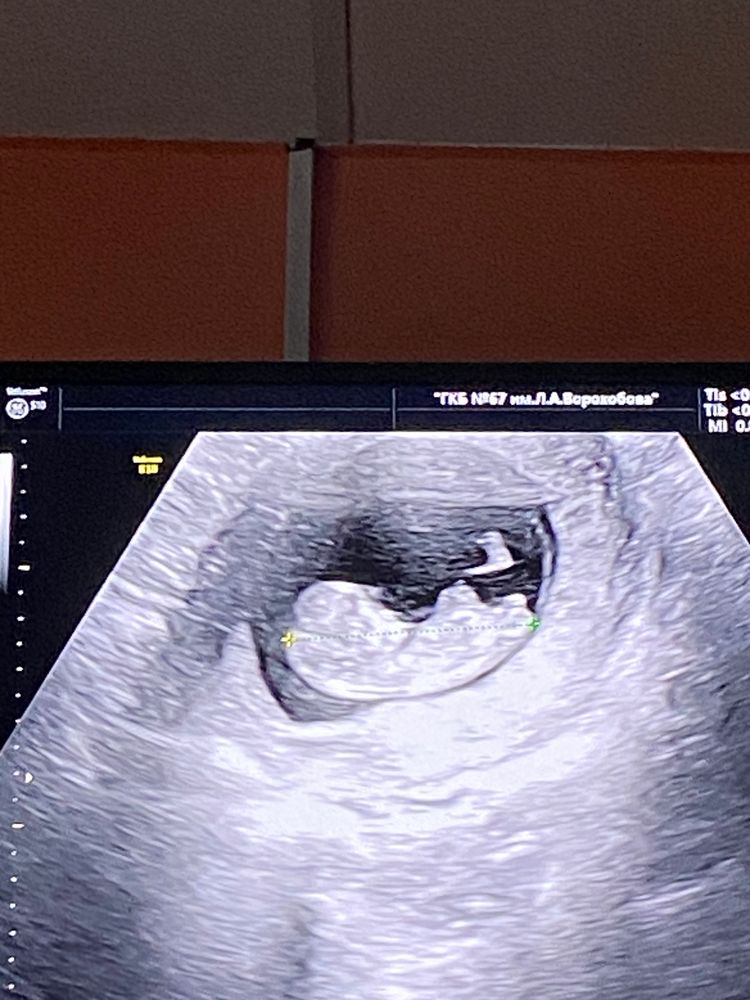

Мальчик или девочка?

Знаю, как-то по тазовым костям определяют и по лбу 🙈🙈🙈 По лбу вроде мальчик, по костям не совсем понятно.

В 10 недель увидели мальчика?

bravo gun, предположили, если приблизить второе фото, то кажется, что реально оно 😁

Лина, а на скрининге что сказали ? В 10 недель нереально)

bravo gun, сказали ждать второго скрининга 😁